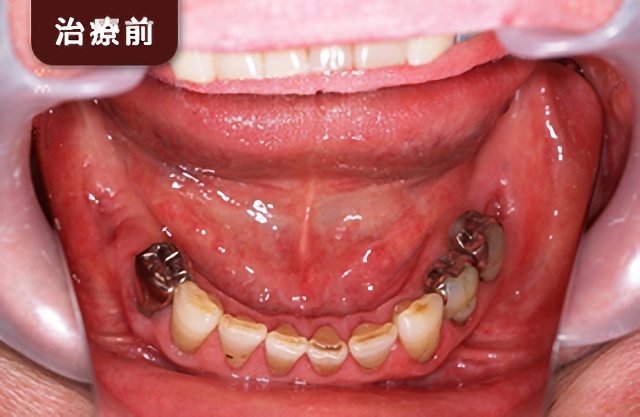

| 総入れ歯 | インプラント |

|---|---|

![]() | ![]() |

| 入れ歯が口の中で動いてしまい、「噛みづらい」や「話しづらい」などの不便さを感じることがあります。 | インプラントにより、入れ歯をしっかりと固定できるので、入れ歯を気にせず食事や会話を楽しむことができます。 |